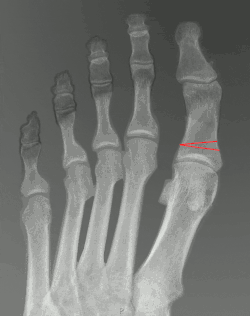

Illustration showing Akin osteotomy correction of the big toe

The surgery is often performed under local anaesthesia. Through a small incision made on the medial side of the big toe, a wedge-shaped piece of the bone is removed from the proximal phalynx. The toe is then realigned to its correct position and secured using pins, screws or a plate.